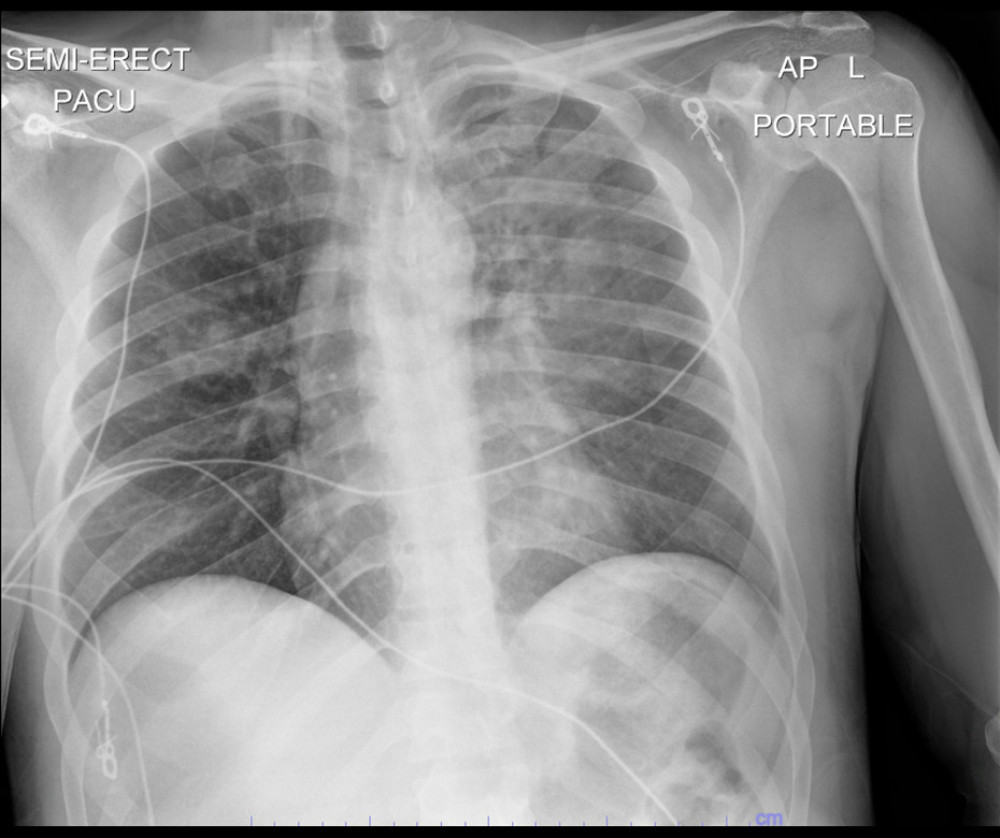

Blastomycosis Dog Chest X Ray . the clinical spectrum of pulmonary blastomycosis is diverse, ranging from. A miliary nodular pattern is present. blastomycosis is a systemic fungal infection caused by the dimorphic fungus blastomyces dermatitidis. blastomycosis should be considered in dogs with draining cutaneous nodules and clinical signs of respiratory disease. Objective —to identify radiographic patterns in dogs with pulmonary. The infective form of the. right lateral radiograph of a dog with blastomycosis. In cats, respiratory tract involvement occurs most frequently, followed by involvement of the cns, regional lymph nodes, skin, eyes, and gi and urinary tracts.

A miliary nodular pattern is present. The infective form of the. blastomycosis is a systemic fungal infection caused by the dimorphic fungus blastomyces dermatitidis. the clinical spectrum of pulmonary blastomycosis is diverse, ranging from. Objective —to identify radiographic patterns in dogs with pulmonary. right lateral radiograph of a dog with blastomycosis. In cats, respiratory tract involvement occurs most frequently, followed by involvement of the cns, regional lymph nodes, skin, eyes, and gi and urinary tracts. blastomycosis should be considered in dogs with draining cutaneous nodules and clinical signs of respiratory disease.